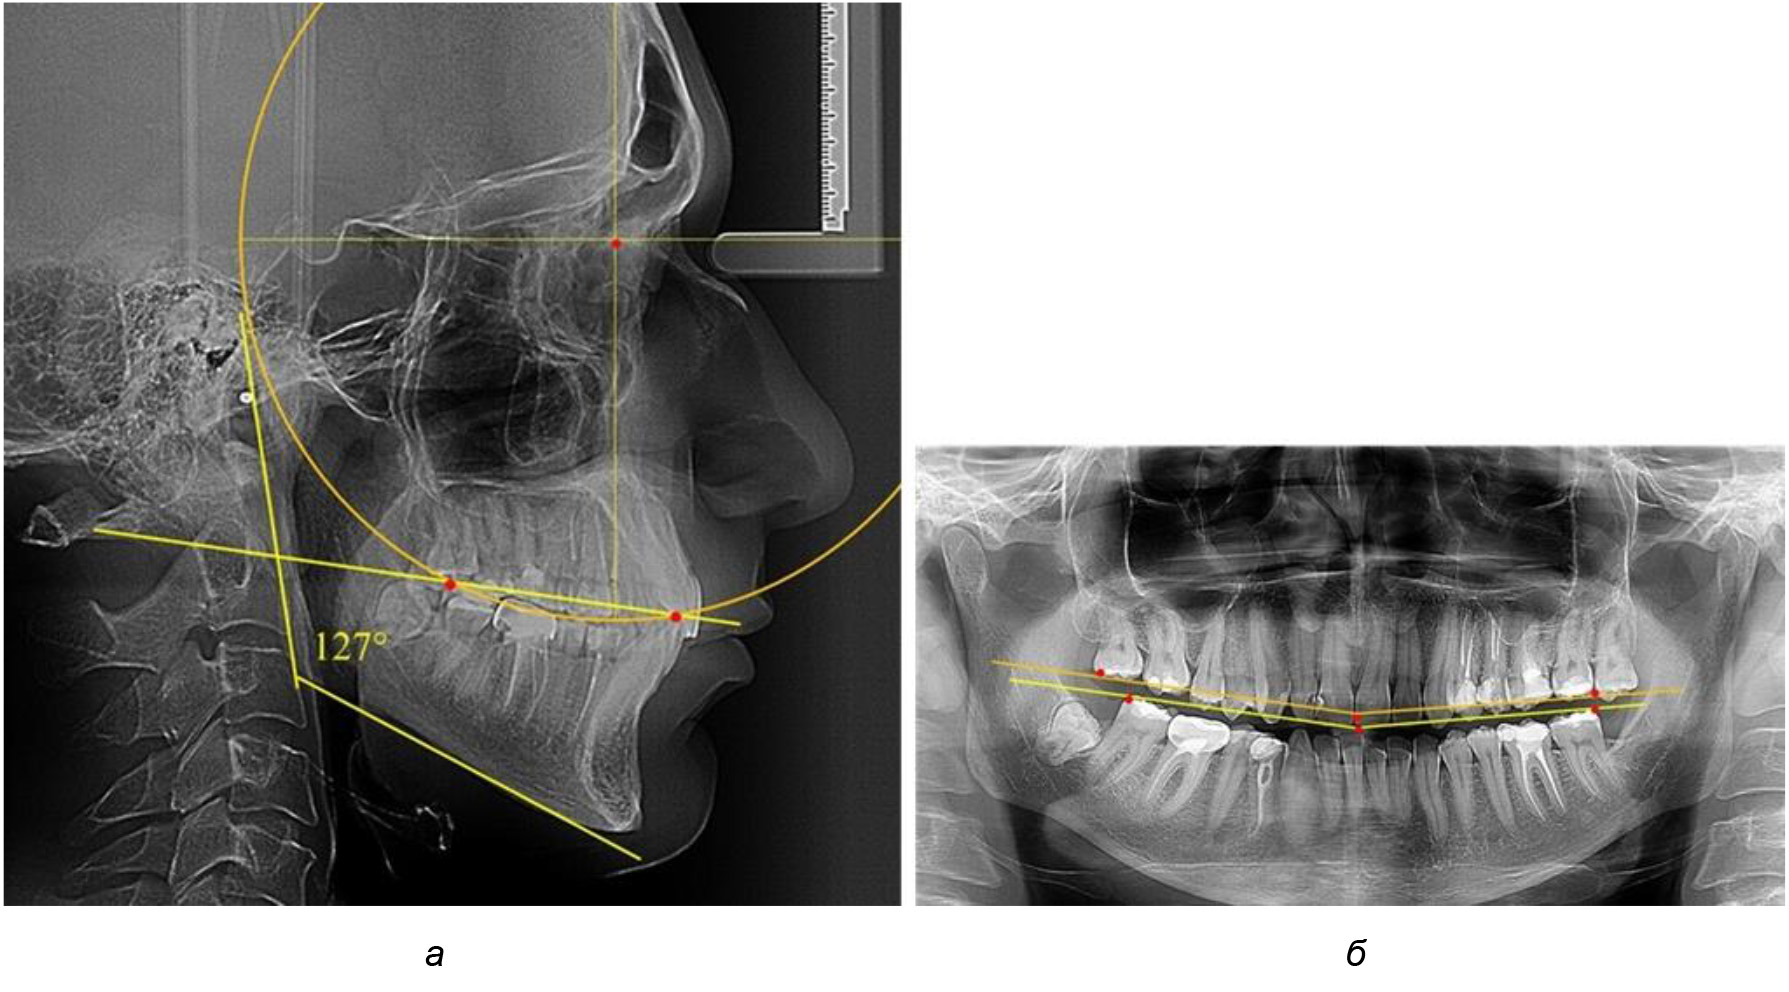

После лечения пациентов техникой «прямой» дуги, так же как и в 1-й подгруппе, было отмечено увеличение сагиттального размера окклюзионной лини в среднем на (2,38 ± 0,83) мм. Окклюзионная линия практически касалась окклюзионного контура всех жевательных зубов, и отмечалось практически полное отсутствие кривой Spee, так же как и у людей 1-й подгруппы 2-й группы (рис. 6).

Рис. 6. Особенности ТРГ при оптимальной кривой Spee до лечения (а) и после лечения (б) техникой «прямой» дуги

Таким образом, проведенное лечение техникой «прямой» дуги способствует нормализации окклюзионного равновесия и торку передних зубов, однако не соответствует оптимальному окклюзионному статусу, характеризующему физиологическую окклюзию. При этом величина нижнечелюстного угла оставалась на прежнем уровне.